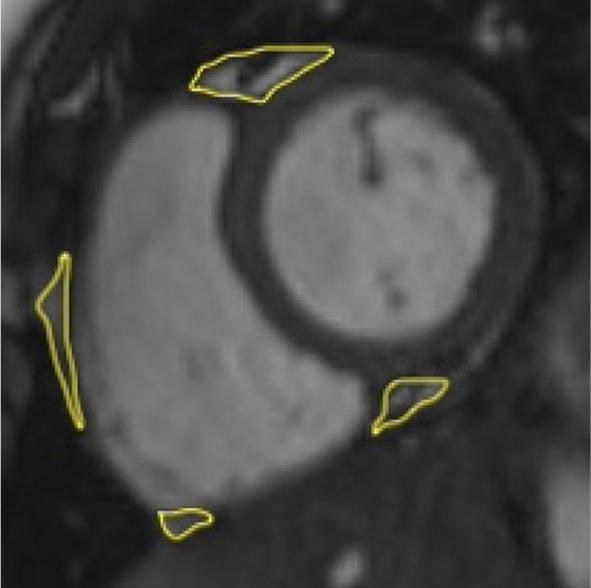

Epicardial adipose tissue (EAT) is a biologically active visceral brown adipose tissue, which is irregularly distributed across myocardium. It has emerged as a potential modifiable cardiometabolic biomarker in adults, demonstrating pro-inflammatory properties with involvement in subclinical atherosclerosis. The increased thickness of the inner two layers of the carotid artery wall (intima and media) in childhood can pose as a risk of the development of atherosclerotic disease and its complications in adult life, representing additional potential biomarker. The purpose of our study was to evaluate a relation between EAT volume (EATV) and carotid intima-media thickness (cIMT) in children and adolescents who have been diagnosed with primary arterial hypertension (AH), utilizing magnetic resonance imaging (MRI).

Children diagnosed with AH exhibited a significantly higher EATV (16.5 ± 1.9 cm . 10.9 ± 1.5 cm; t = -13.815, p < 0.001) and higher cIMT (0.7 [0.2] mm . (0.4 [0.1) mm]; U = 54, p < 0.001) compared with their healthy counterparts. EATV demonstrated a significant correlation with cIMT.

Increased EATV and cIMT were found with MRI in hypertensive children compared to their healthy counterparts. EATV demonstrated a stronger association with hypertension than cIMT. EATV emerged as an independent predictor of cIMT.